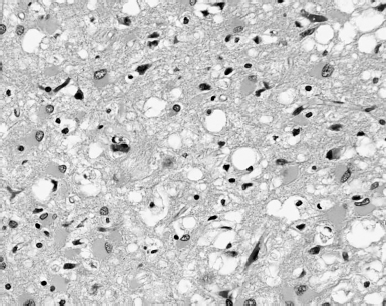

The exploded pingos and open melt lakes of the Siberian plain, seen from the air, resemble brain scans of spongiform encephalopathy patients, their cortexes pitted and scarred by the death of nerve cells. The prion diseases that cause spongiform encephalopathy – scrapie, kuru, mad cow disease, CJD and their derivatives – are the result of misfolded proteins, scraps of base matter that have become twisted into malformed shape. They spread themselves through the body by converting their properly folded counterparts into their own image. When prion infections reach the brain, they cause rapid-onset dementia, memory loss, personality changes, hallucinations, anxiety, depression, and ultimately death. The brain itself comes to resemble a sponge, hollowed out and denatured, unable to make sense of itself and its end. The permafrost – the permanent frost – is melting. The words don’t make sense any more, and with them go the ways we have to think the world.

Images

Source: Public Health Image Library (ID#: 10131).

Light photomicrograph of brain tissue (magnified 100X) suffering from CJD.